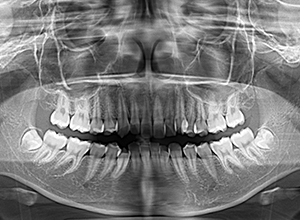

| パノラマ所見 | 上顎両側第三大臼歯は欠損、下顎第三大臼歯は埋伏していた。 |